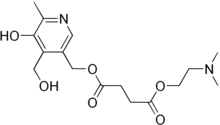

| Formula | C16H24N2O6 |

| Molar mass | 340.376 g·mol−1 |

Pirisudanol (Mentis, Menthen, Mentium, Nadex, Nadexen, Nadexon, Pridana, Stivane), also known as pyrisuccideanol, is the succinic acid ester of pyridoxine (a form of vitamin B6) and of deanol (DMAE).[1] It has been used in Europe in the treatment of mild cognitive impairment as well as fatigue and depression.[1][2][3][4][5]